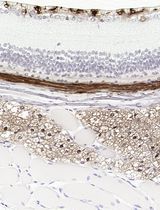

Figure 5. Representative images of spheroids up to 96 h (10× magnification)

1. Spheroid formation and consistency: Using the agarose-coated plates described, we consistently formed compact, spherical aggregates within 24 h. The spheroids remained stable and did not increase in size over the 96-h culture period (Figures 5 and 8). This stability makes the model optimal for drug testing, where changes in spheroid size can be used as a reliable readout.